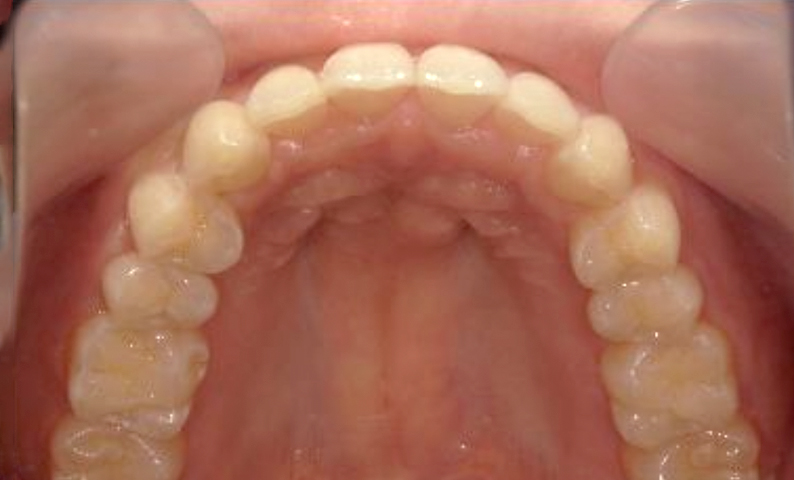

| 治療前 | 治療後 |

|---|---|

|